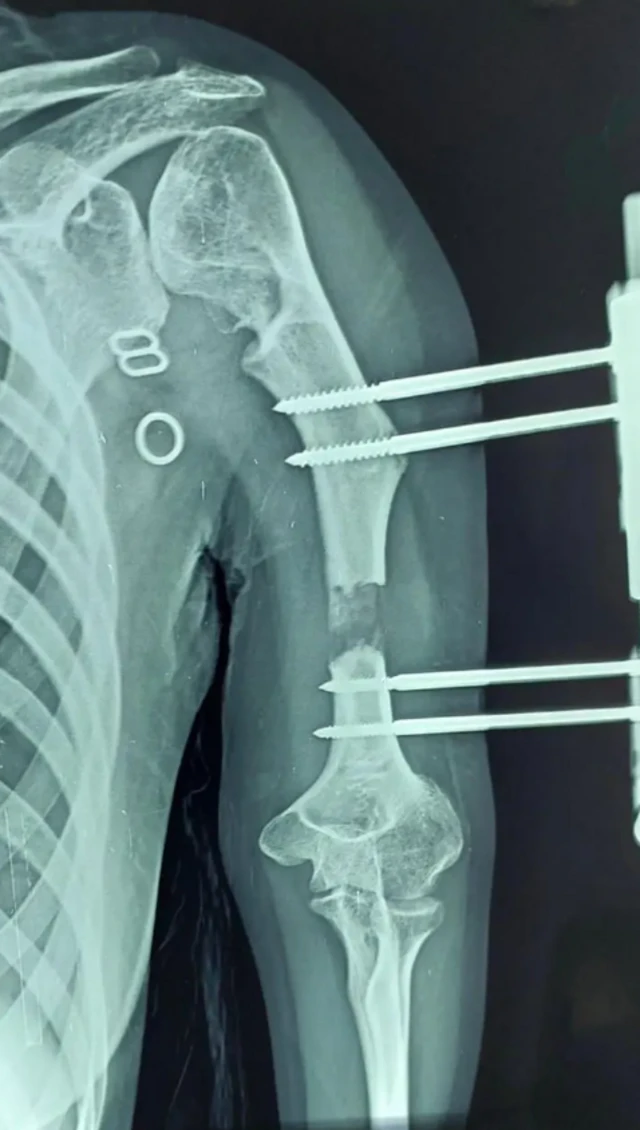

ਡਾਕਟਰ ਸੁਰੇਸ਼ ਕਹਿੰਦੇ ਹਨ, "ਅਸੀਂ ਪਹਿਲਾਂ ਵਿਗਿਆਨਕ ਤੌਰ 'ਤੇ ਵਿਕਾਸ ਸਬੰਧੀ ਨੁਕਸ ਵਾਲੇ ਵਿਅਕਤੀ ਦੀ ਹੱਡੀ ਨੂੰ ਤੋੜਦੇ ਹਾਂ। ਫਿਰ ਇੱਕ ਬਾਹਰੀ ਫਿਕਸੇਟਰ ਮਰੀਜ਼ ਦੀ ਹੱਡੀ ਨਾਲ ਜੋੜਿਆ ਜਾਂਦਾ ਹੈ ਅਤੇ ਪੇਚ ਲਗਾਏ ਜਾਂਦੇ ਹਨ।''

''ਇਹ ਯੰਤਰ ਮਰੀਜ਼ ਦੀ ਚਮੜੀ ਦੇ ਬਾਹਰ ਹੁੰਦਾ ਹੈ। ਜਦੋਂ ਯੰਤਰ ਨੂੰ ਹਰ ਰੋਜ਼ ਘੁੰਮਾਇਆ ਜਾਂਦਾ ਹੈ, ਤਾਂ ਹੱਡੀ ਇੱਕ ਝਿੱਲੀ ਵਾਂਗ ਫੈਲ ਜਾਂਦੀ ਹੈ। ਜਦੋਂ ਤੁਸੀਂ ਇਸ ਨੂੰ ਖਿੱਚਦੇ ਹੋ ਤਾਂ ਹੱਡੀ ਵਿੱਚ ਰਬੜ ਬੈਂਡ ਵਰਗੀ ਲਚਕਤਾ ਹੁੰਦੀ ਹੈ।''

ਸਰਜਰੀ ਤੋਂ ਦਸ ਦਿਨਾਂ ਬਾਅਦ, ਬਾਹਰੀ ਯੰਤਰ ਵਿੱਚ ਪੇਚ ਵਰਗੀ ਬਣਤਰ ਨੂੰ ਕੱਸਣ ਨਾਲ ਹੱਡੀ ਝਿੱਲੀ ਵਾਂਗ ਫੈਲਦੀ ਹੈ।

ਜਦੋਂ ਯੰਤਰ ਦੀ ਪੇਚ ਵਰਗੀ ਬਣਤਰ ਨੂੰ ਦਿਨ ਵਿੱਚ ਹਰ ਛੇ ਘੰਟਿਆਂ ਵਿੱਚ ਇੱਕ ਵਾਰ ਘੁੰਮਾਇਆ ਜਾਂਦਾ ਹੈ, ਤਾਂ ਅੰਦਰਲੀ ਹੱਡੀ ਹੇਠਾਂ ਵੱਲ ਖਿੱਚੀ ਜਾਂਦੀ ਹੈ ਅਤੇ ਵਧਦੀ ਹੈ। ਇਸ ਬਣਤਰ ਨੂੰ ਪੇਚ ਕਰਨ ਦੀ ਪ੍ਰਕਿਰਿਆ (ਪੇਚ ਘੁੰਮਾਉਣ ਦੀ ਪ੍ਰਕਿਰਿਆ) ਇੰਨੀ ਸਰਲ ਹੈ ਕਿ ਮਰੀਜ਼ ਇਸ ਨੂੰ ਖੁਦ ਕਰ ਸਕਦੇ ਹਨ।

ਇਹ ਡਿਸਟਰੈਕਸ਼ਨ ਓਸਟੀਓਜੇਨੇਸਿਸ ਨਾਮਕ ਇੱਕ ਇਲਾਜ ਤਹਿਤ ਕੀਤਾ ਜਾਂਦਾ ਹੈ। ਇਸ ਇਲਾਜ ਵਿੱਚ, ਹੱਡੀ ਪ੍ਰਤੀ ਦਿਨ ਇੱਕ ਮਿਲੀਮੀਟਰ ਦੀ ਦਰ ਨਾਲ ਇੱਕ ਝਿੱਲੀ ਵਾਂਗ ਵਧਦੀ ਹੈ, ਭਾਵ ਇੱਕ ਸੈਂਟੀਮੀਟਰ ਵਧਣ ਵਿੱਚ ਦਸ ਦਿਨ ਲੱਗਦੇ ਹਨ।

ਗੋਮਤੀ ਦੀ ਹੱਡੀ ਨੂੰ 14 ਸੈਂਟੀਮੀਟਰ ਤੱਕ ਵਧਣ ਵਿੱਚ 140 ਦਿਨ ਲੱਗੇ। ਫਿਰ ਖਿੱਚੀ ਹੋਈ ਝਿੱਲੀ ਨੂੰ ਹੱਡੀ ਵਾਂਗ ਮਜ਼ਬੂਤ ਬਣਨ ਵਿੱਚ ਦੁੱਗਣੇ ਦਿਨ ਲੱਗਦੇ ਹਨ, ਭਾਵ - 280 ਦਿਨ।

ਉਨ੍ਹਾਂ ਕਿਹਾ, "ਗੋਮਤੀ ਦੀ ਦਿੱਕਤ ਵਾਲੀ ਬਾਂਹ ਵਿੱਚ ਹੱਡੀ ਪਹਿਲਾਂ 14 ਸੈਂਟੀਮੀਟਰ ਲੰਬੀ ਸੀ। ਹੁਣ, 14 ਸੈਂਟੀਮੀਟਰ ਹੋਰ ਵਧਣ ਨਾਲ, ਇਹ ਕੁੱਲ 28 ਸੈਂਟੀਮੀਟਰ ਲੰਮੀ ਹੋ ਗਈ ਹੈ ਅਤੇ ਆਮ ਵਾਂਗ ਦਿਖਾਈ ਦਿੰਦੀ ਹੈ। ਨਾ ਸਿਰਫ਼ ਹੱਡੀ, ਸਗੋਂ ਚਮੜੀ, ਖੂਨ ਦੀਆਂ ਨਾੜੀਆਂ ਅਤੇ ਨਸਾਂ ਵੀ ਇਸਦੇ ਨਾਲ ਵਧੀਆਂ ਹਨ।''